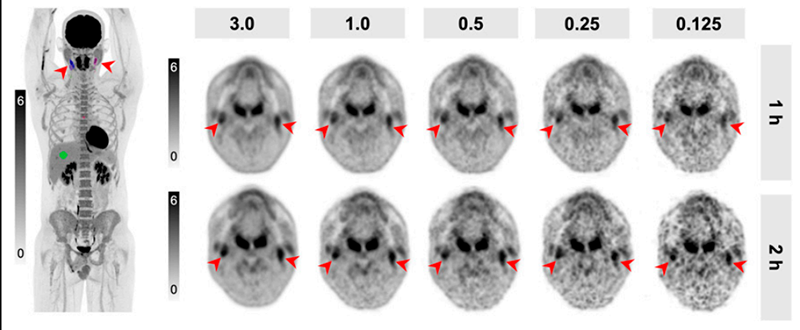

Lymphoma Therapy Response Assessment with Low-Dose [18F]FDG Total-Body PET/CT

The improved sensitivity of total-body (TB) PET/CT offers the possibility of reducing injected activities. The aim of our study was to define a lower limit of reduced injected activities in [18F]FDG TB PET/CT for interim and end-of-treatment assessment of patients with lymphoma at 2 acquisition times. Dose reduction of injected activity in patients with lymphoma is possible with TB PET/CT, reducing the radiation burden for young or pregnant patients, who undergo multiple consecutive PET scans during their treatment for response assessment.

Mingels et al., J Nucl Med. 2025